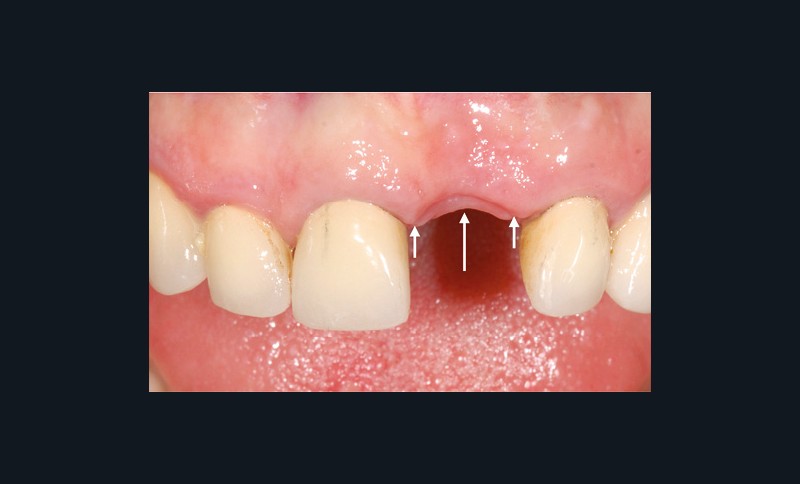

Lorsque la crête est déjà édentée, la résorption osseuse a déjà eu lieu et, en conséquence, la morphologie des tissus mous est altérée (fig. 1). Il faut alors utiliser des techniques d’augmentation osseuse et/ou muqueuse afin d’obtenir une architecture des tissus mous la plus naturelle possible.